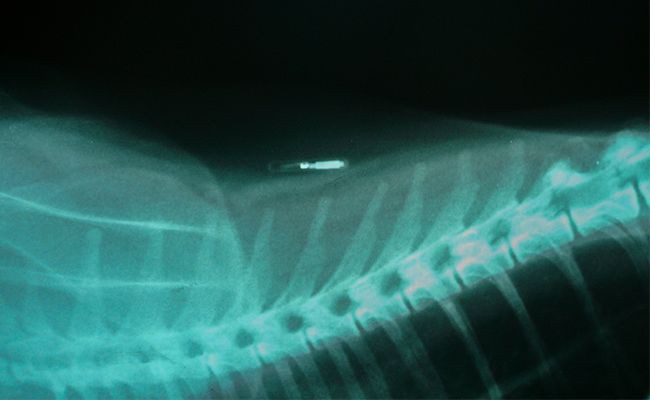

Microchipping a dog procedure

A small chip is placed, normally between the shoulder, using a clean needle. A distinct and unique number on the chip enables it to be picked up by a scanner.